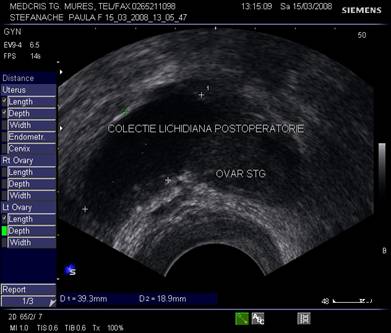

Fig. nr.391.

Endometriom ovarian vechi ,recidivat postoperator,

situat retrouterin

( sageata ). Se remarca ecogenitatea crescuta si asemanatoare ecostructurii endometriale uterine.